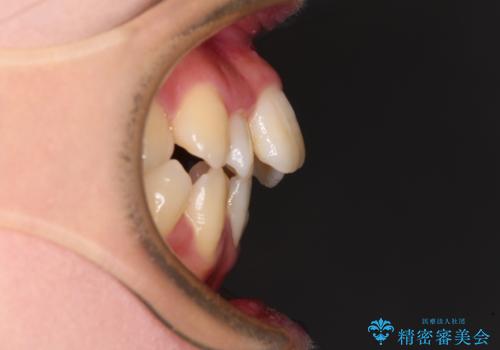

デコボコと出っ歯 抜歯矯正でスッキリとした口元に

- 上下前歯の八重歯やデコボコと、唇の閉じにくさを気にして来院された患者様です。

口元の突出感を改善するため、上下左右の第一小臼歯4本を抜歯し、ワイヤー装置にて矯正治療を行うこととしました。